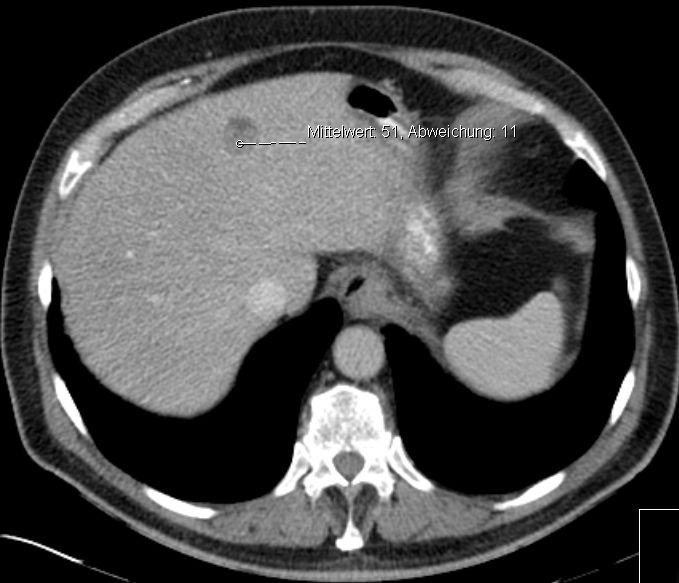

| Lebermetastasen | 72-jähriger Mann, der vor 2 Jahren ein Melanom des linken Schulterblattes hatte.

1 Jahr Interferon-A. Jetzt Lebermetastase.![]() | |||